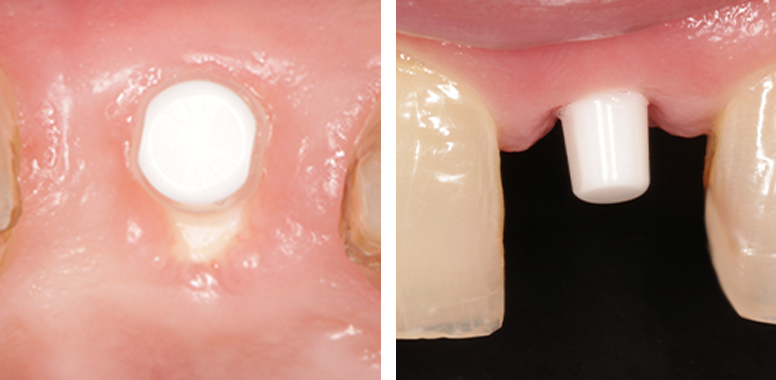

Healthy Gums with Biocompatible Ceramic Implants

Seamless Integration with Metal-Free Implants: Invisible Esthetics for a Natural-Looking Smile

How do zirconia implants promote soft tissue health?

Zirconia’s smooth, ceramic surface encourages healthy gum tissue growth around the implant. Unlike metal implants, zirconia does not interfere with the natural healing process. At Byond Dental, patients in Metro Detroit trust us for biocompatible implants that support both oral and overall health.

Made from white ceramic, zirconia implants offer a natural, tooth-like appearance with no dark metal lines or shadows. Patients at Byond Dental love their ability to restore confidence with a flawless, biomimetic smile.

• Enhanced soft tissue health with smooth, biocompatible surfaces